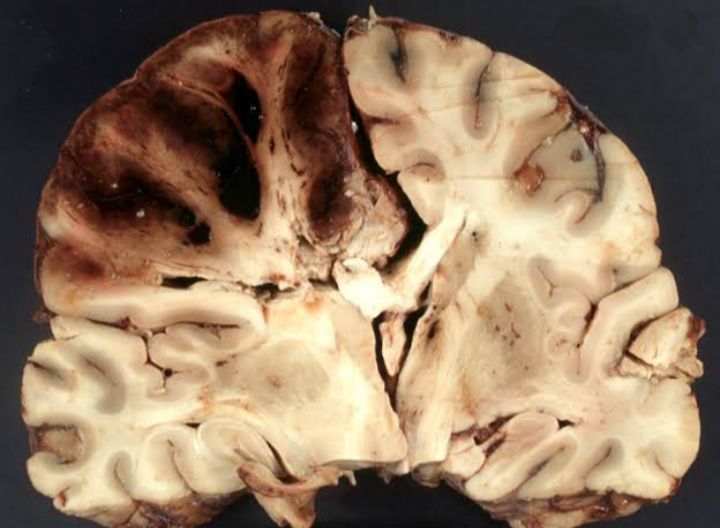

Cerebrovascular disease

Cerebrovascular disease includes group of conditions that affect blood vessels and blood flow to brain. Problems with blood flow may occur from stenosis ,thrombosis,embolism , also Haemorrhage.